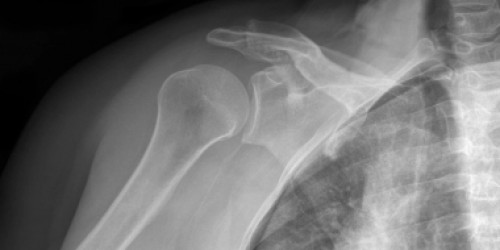

I had a Bankart fracture of my right shoulder in April. I am three months out and still have pain, especially at night. My arm position wakes me up every few hours. It is a really frustrating fracture....Any help would be appreciated.